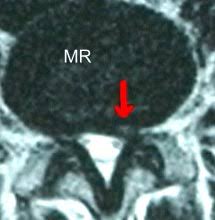

Auf dem MRT erkennt man ein deutliches Narbengewebe. Narbengewebe nach Bandscheiben-OP Zunächst sollte geklärt werden ob die Beschwerden tatsächlich vom Narbengewebe kommen. Habe vor einem Jahr Bandscheiben OP bei L45 mit anschließend 6 Wochen nicht sitzen und darauf 5 Wochen Reha gehabtDie eigentl.